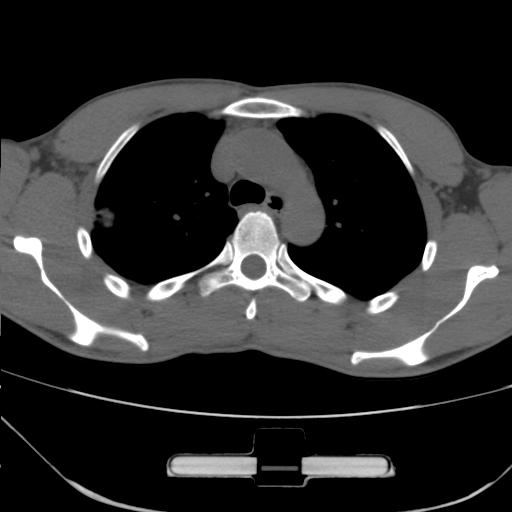

右肺上叶后段近胸膜下结节样异常密度灶,似见分页及毛刺,考虑右肺上叶周围型肺ca,建议穿刺病理检查

缺乏病史,症状体征,但这个孤立结节具备了几乎所有的恶性征象:分叶,毛刺,空泡征,胸膜凹陷征,血管集束。

考虑右肺上叶后段周围型肺癌。